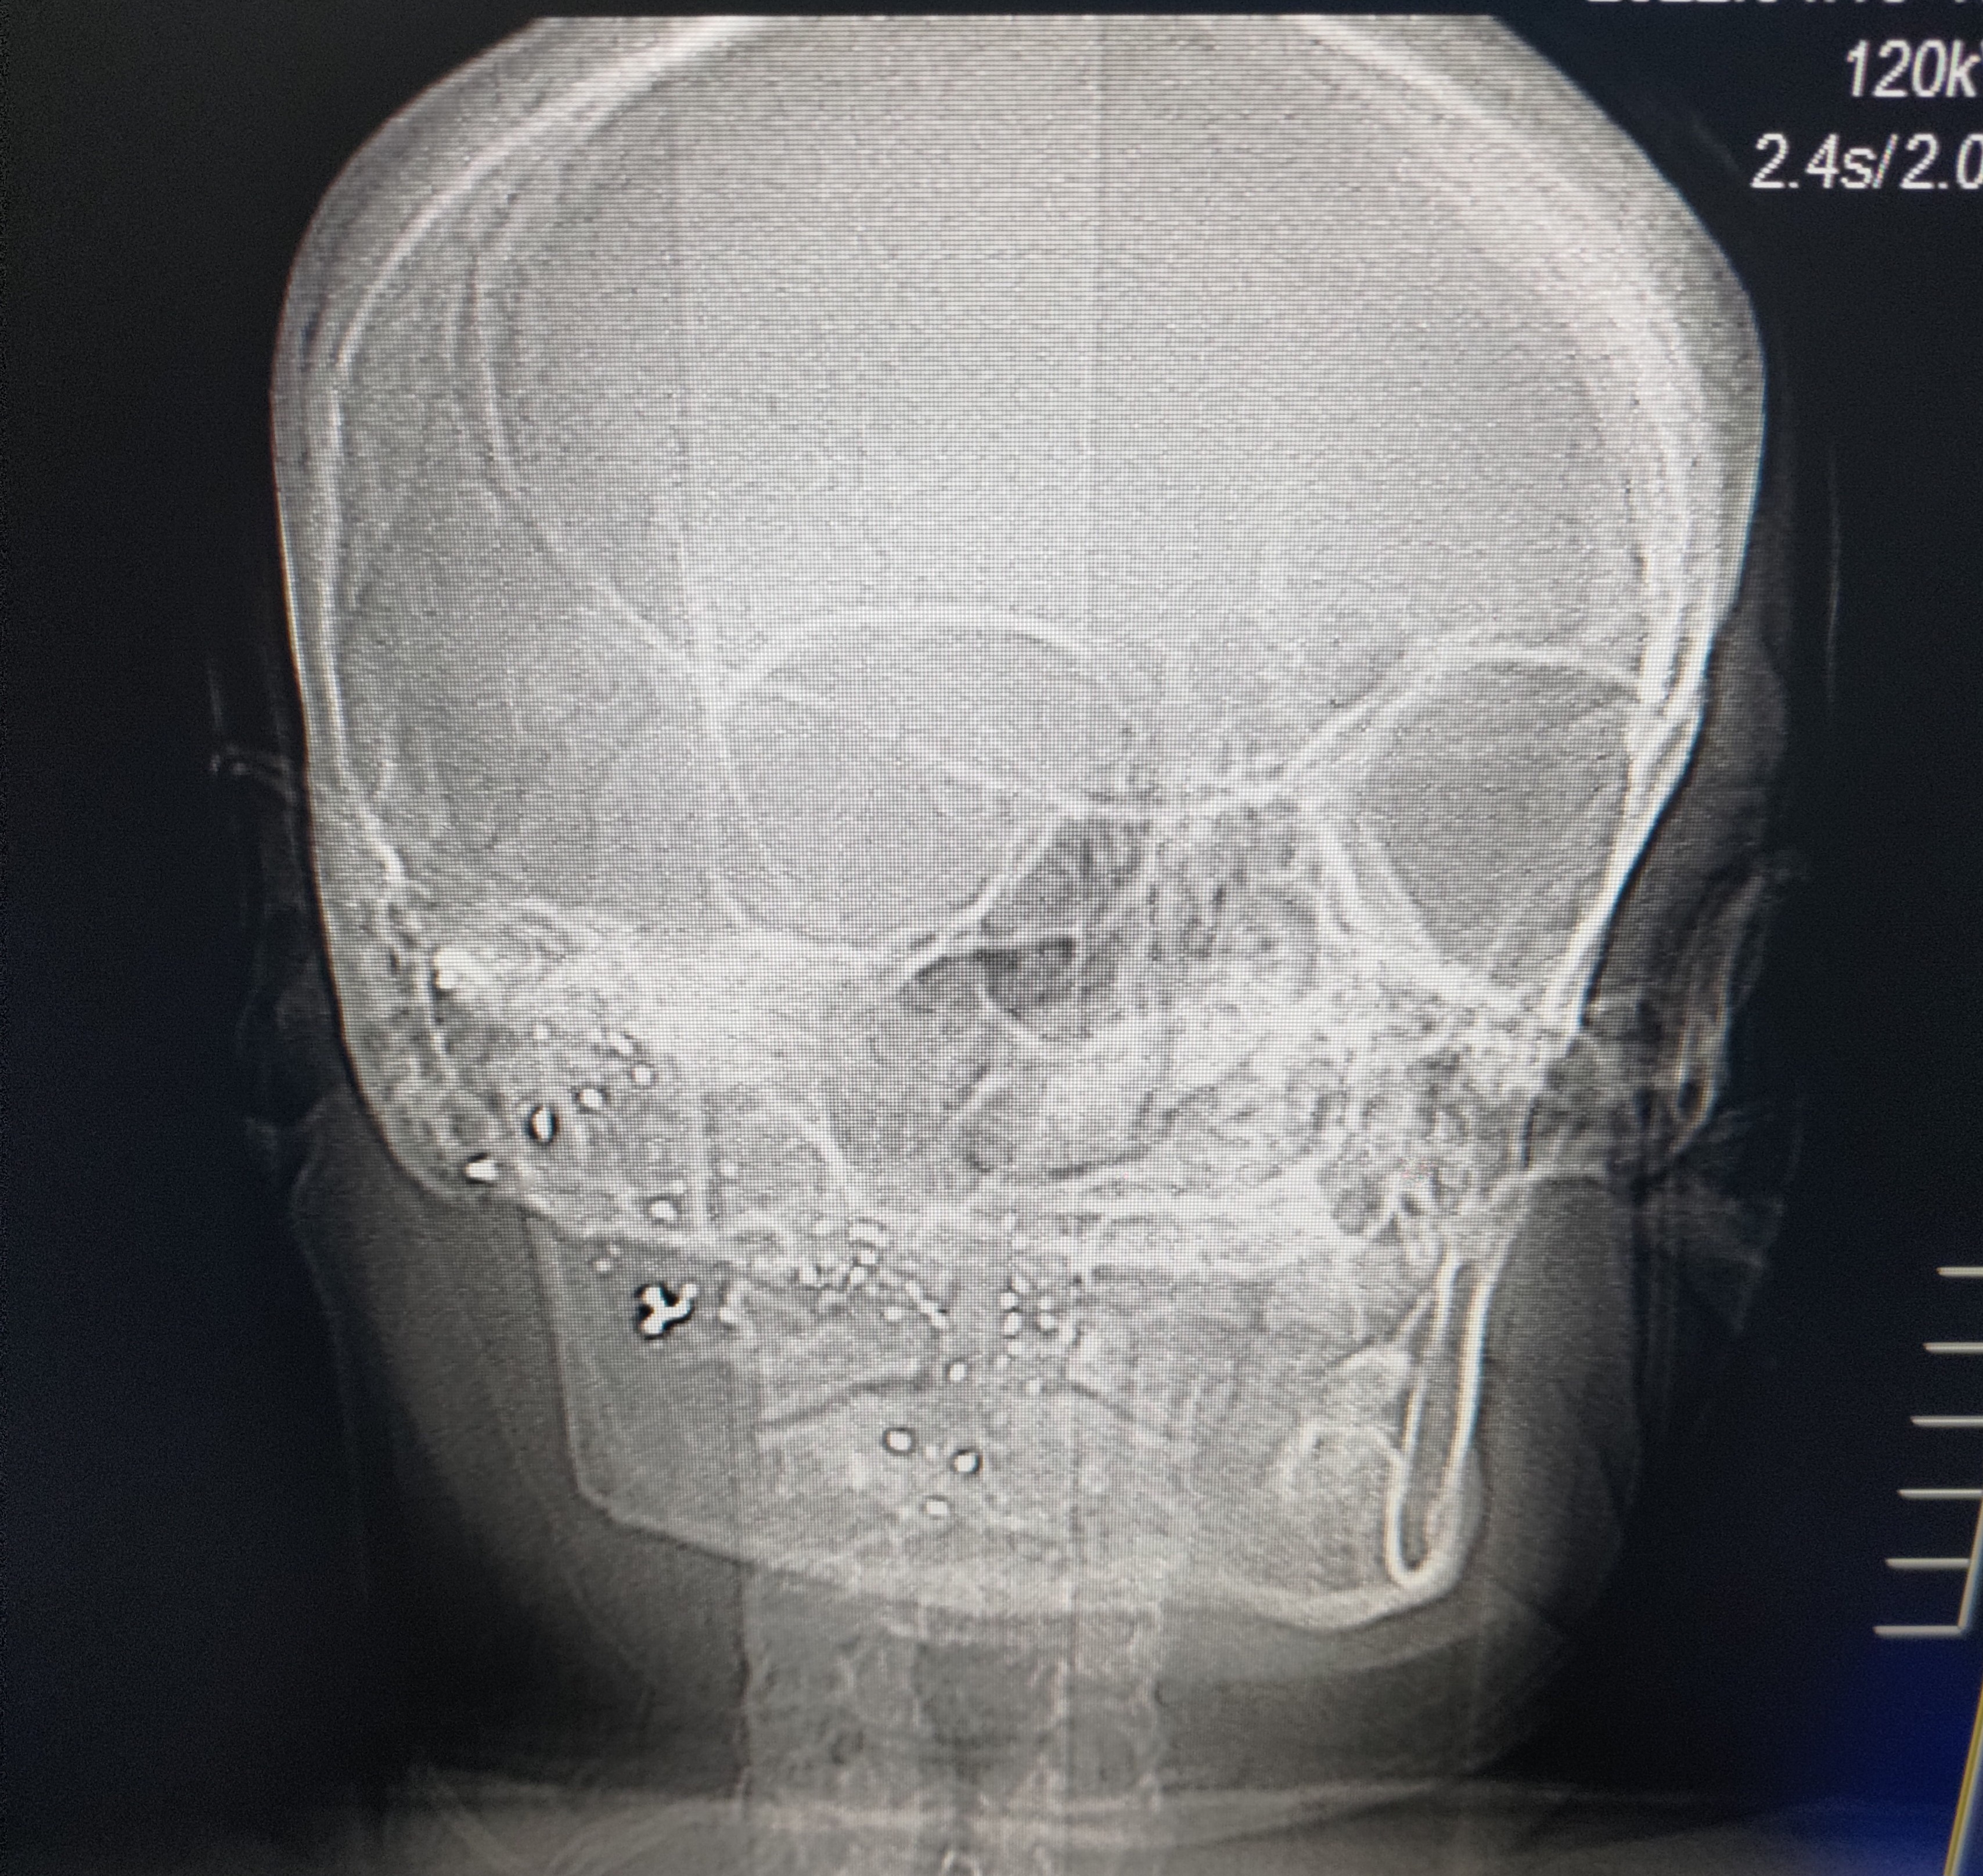

File: P_20220413_182801_1.jpg (2.86 MB, 3415x3231)

>>64449187

You're not retarded, you just haven't worked in trauma centers in major cities where you see this shit all the time. Here's a guy who got shot in the face with birdshot (no idea what gauge shotgun) and came strolling on into my CT room years later because he had a headache. You literally wouldn't have known he was shot if you looked at his face. He forgot his key and was trying to break into his own house through the window one night when his next door neighbor came out and shot him thinking he was a burglar. A great case for why you should have a WML, and never use birdshot for anything but birds.

A great number of folks over estimate how much damage handgun rounds do to people. Bullets do weird whacky shit man, carrying hollow points helps you maximize your chances of eliminating your target. Using a rifle with a WML for home defense is also a great take away lesson.